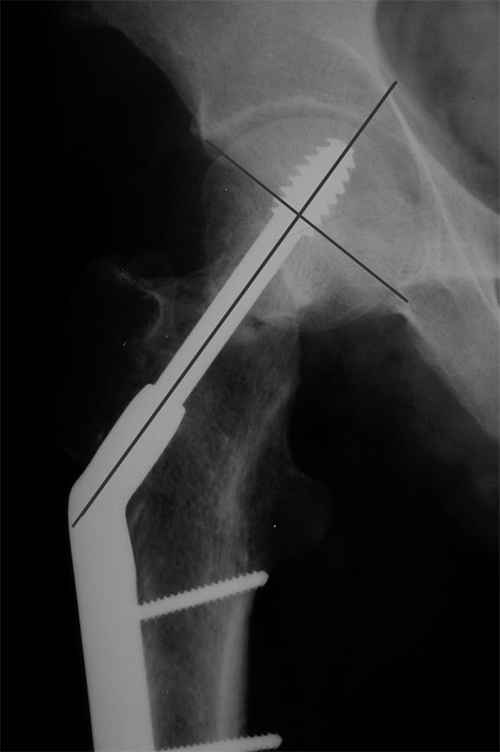

Больной Т. 1966 г.р.Травма 28.06.2007. Прооперирован в г. Бишкек, Оп: Остеосинтез правого бедра системой DHS. В последующем беспокоили периодические боли в правом тазобедренном суставе с иррадиацией в коленный сустав в область передней поверхности правого бедра. Лечился амбулаторно с незначительным эффектом. В 07.04.2008 по 08.05.2008 года лечился в госпитале ГУВД и СО в стационаре с Срастающийся перелом шейки правого бедра в условиях фиксации системой DHS – боли уменьшились.Боли обострились 03.02.2009 внезапно, госпитализирован. Результат - Псевдоартроз шейки правого бедра (имеются косвенные признаки разрушения спонгиозной части головки бедра)Планируется - Работает милиционером. Имеющийся опыт протезирования у данной категории во всех случаях в ближайшее время заканчивался дисквалификацией. Работоспособный возраст (43 года).Наиболее приемлемым и реальным методом лечения предполагается: Удаление конструкций из бедра. Заполнение полости от винта монолитным аутотрансплантатом из крыла (крылев) подвздошной кости. Медиализация большого вертела. Предполагаемый период нетрудоспособности 3-4 мес.

На более раннем снимке репозиция была, мягко говоря, далека от идеальной. Плюс перелом шейки слишком проксимальный для фиксации одном винтом. Неудача тут закономерный исход.

Но в данном случае DHS сыграл как имплант с угловой стабильностью, что привело к прорезыванию импланта в верхнем сегменте головки. Отсутствие трехточечной опоры и длинный имплант увеличивают нестабильность в шейке.

Если на рентгенограмме произошли изменения положения импланта более чем на 5 градусов от первоначального, миграция шурупов более чем 15 мм от кортекса, также потеря репозиции на 10 мм - это свидетельство несостоятельности импланта. Компьютерная томография уточнит все сомнения. В таких случаях бесполезно ожидать, что перелом срастется, лучше своевременно сообщить больному и принимать решительные меры по реконструкции.

Коллеги правы, что надо делать вальгусную остеотомию с латеризацией диафиза бедра. Рекомендуемая медиализация приведет к вальгусной деформации оси конечности.

Предлагамый монолит из-за трудности проведения Special Chisel для клинка не рекомендуется. Место удаленной конструкции забивается спонгиозной костью из крыла, для предупреждения пенетрации в сустав лучше под экраном.